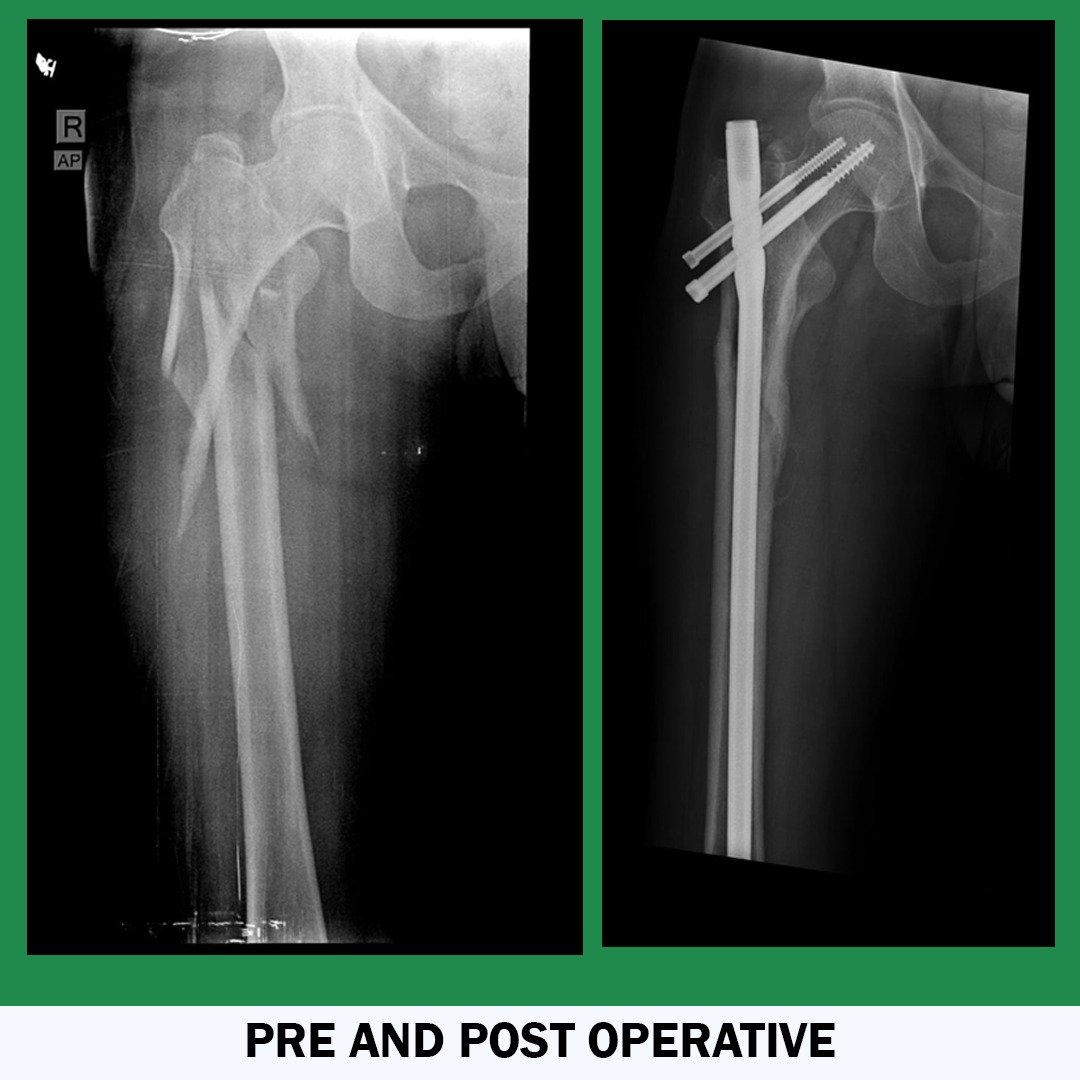

• Orthopedic Trauma Specialist

Dr Ashok K. Sharma is a fully qualified, highly trained, and well-experienced orthopaedic surgeon in India. His Specialization is knee, hip, and shoulder replacement. He is providing the services for more than 13 years. He has performed numerous complicated Joint Replacement and Trauma Surgeries and holds the position of leading Joint Replacement and Arthroscopic surgeon in India. He has done a fellowship in Advance Knee Replacement and Arthroscopic Surgery. Dr. Sharma provides the best consultation on bone-related issues and delivers the best Surgical Outcomes. He is currently associated with Eternal Hospital and Apex Hospital Jaipur, India.